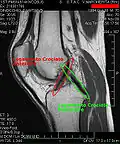

МРТ коленного сустава.

Крестообразные связки.